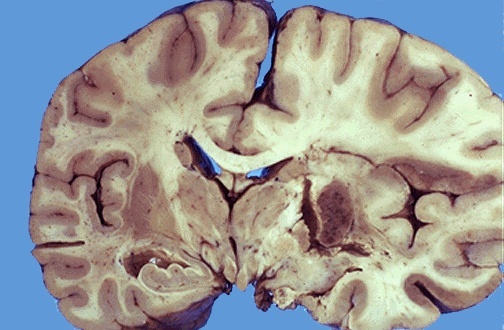

Lacunar infarct - cystic space due to liquefactive necrosis

Cystic space, liquefactive necrosis